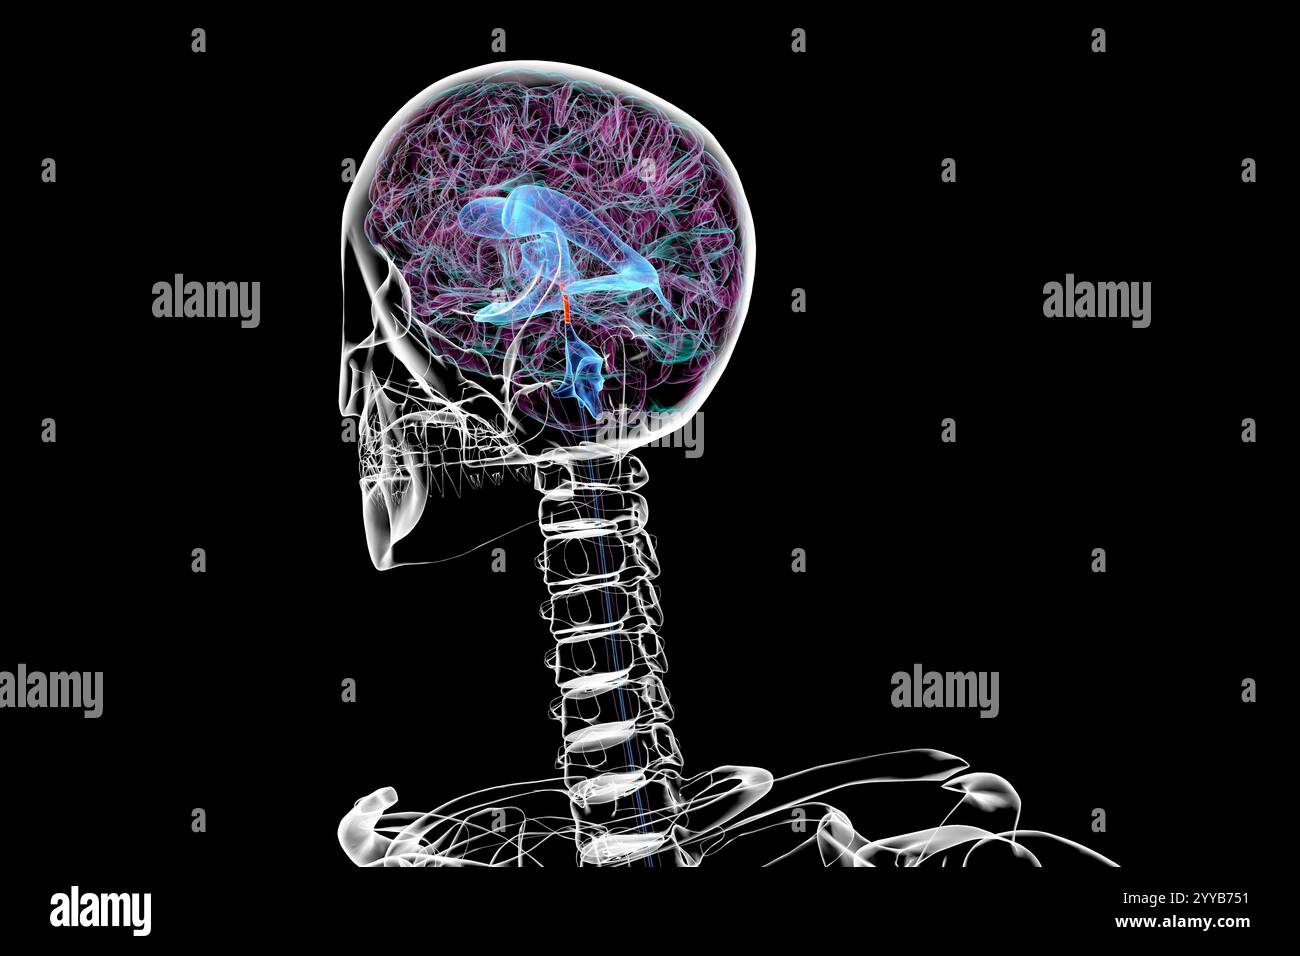

RF2T7NGWH–Ventrikel und zerebrales Aquädukt laterale Röntgenansicht 3D-Rendering-Illustration. Menschliches Gehirn und Ventrikelsystem Anatomie, Medizin, Gesundheitswesen, Scienc

RF2T7NGWK–Ventrikel und zerebraler Aquädukt lateral in Farben Röntgenbild-3D-Rendering-Illustration. Menschliches Gehirn und Ventrikelsystem Anatomie, medizinisch, gesund

RF2T7NGWR–Ventrikel und Hirn-Aquädukt-Röntgenprofil Nahansicht 3D-Rendering-Illustration mit Körperkonturen. Anatomie des menschlichen Gehirns und des Ventrikelsystems,

RF2T7NGWW–Ventrikel und zerebraler Aquädukt in Farben Röntgenprofil Nahansicht 3D-Rendering-Illustration. Anatomie des menschlichen Gehirns und des Ventrikelsystems, medizinisch,

RF2T030FH–Röntgenprofilansicht des Sylvius oder des zentralen Aquädukts des Gehirns 3D-Rendering-Illustration. Menschliche Körperanatomie, Medizin, Biologie, Wissenschaft, Neurowissenschaft,

RF2T6AR8J–3D-Rendering-Illustration für die Röntgenansicht des Gehirns oder des Sylvius aquädukt. Anatomie des menschlichen Gehirns und des Ventrikelsystems, Medizin, Gesundheitswesen, Biologie, Wissenschaft,

RF2T6AR96–Röntgenprofil des Gehirns oder sylvius aquädukt Nahansicht 3D-Rendering-Illustration mit Körperkonturen. Anatomie des menschlichen Gehirns und des Ventrikelsystems, med